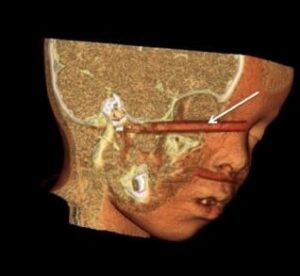

3D-CT reconstruction ofa-child-who-fell-on-a-writing-pen-The-pen-entered-the-right

A CT scan will also show whether there are associated fractures and if the object has penetrated into any deeper structures, such as the brain. If the foreign body is wooden it may not be seen on X-ray or CT, and an MRI scan may be necessary. Emergency Trauma services in Mumbai are available at Wavikar Eye Hospital.

3D-CT reconstruction of a child who fell on a writing pen. The pen entered the right